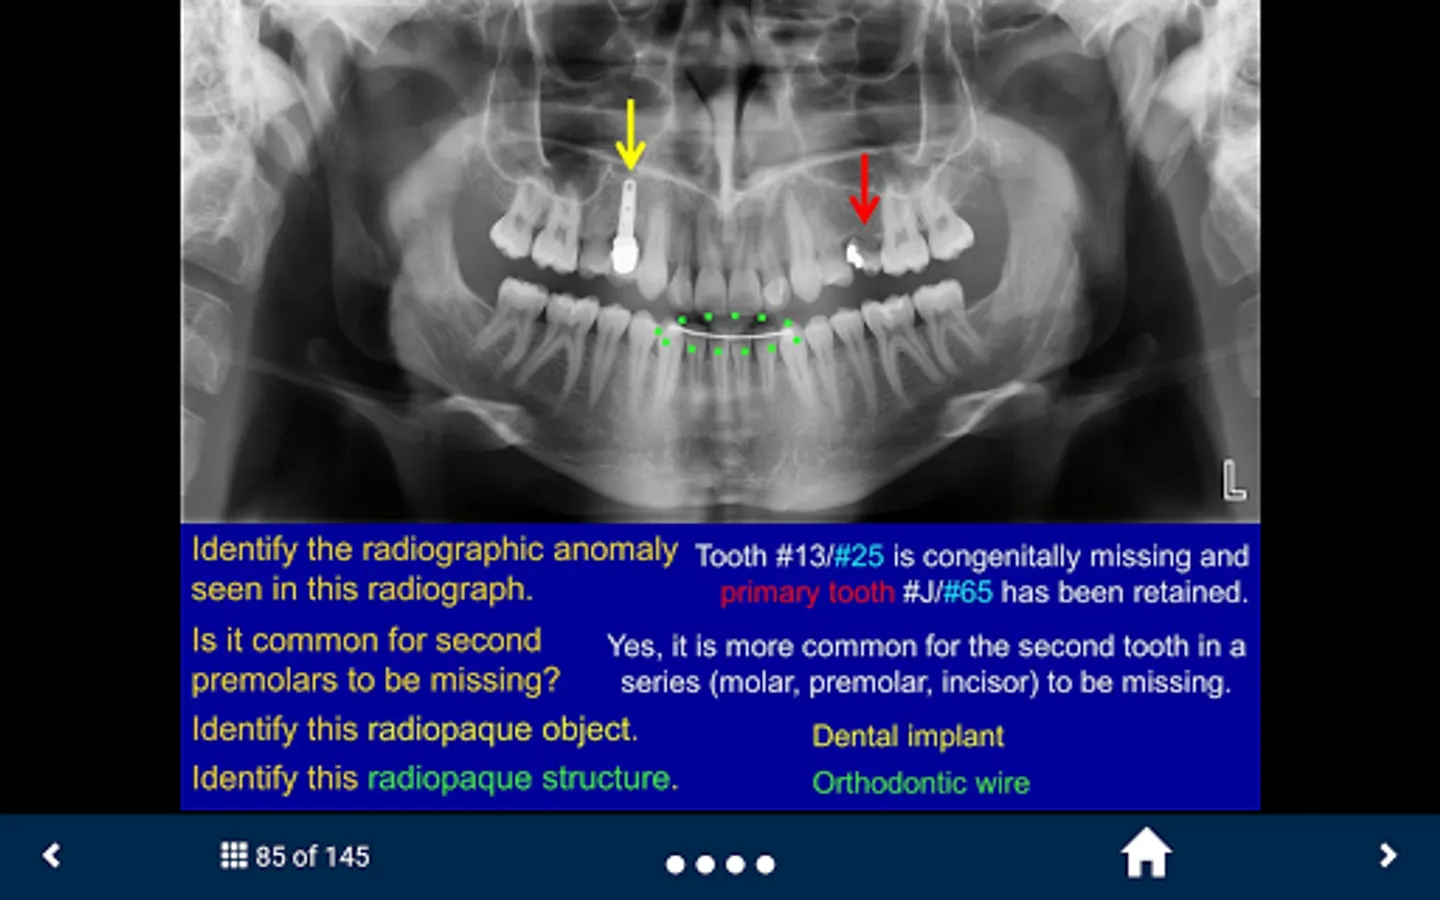

The SecondLook™ Oral Radiology application will help learners of the dental sciences to self-test their level of knowledge and ability to recognize technical errors, anatomical structures, dental disease, and maxillofacial pathology in intraoral and panoramic radiographs as well as CBCT scans. This app covers the following topics: Radiographic Anatomy (on Periapical & Bitewing Radiographs); Radiographic Anatomy (on Panoramic Radiographs); Image Quality and Common Errors; Radiographic Interpretation; Radiographic Anomalies; Buccal Object Rule (BOR); Cone Beam Computed Tomography (CBCT); Pediatric Radiology; and Presentations of Oral Pathologies (including inflammatory lesions, cyst and cyst- like lesions, benign tumors of the jaws, malignant diseases, bone and systemic diseases).